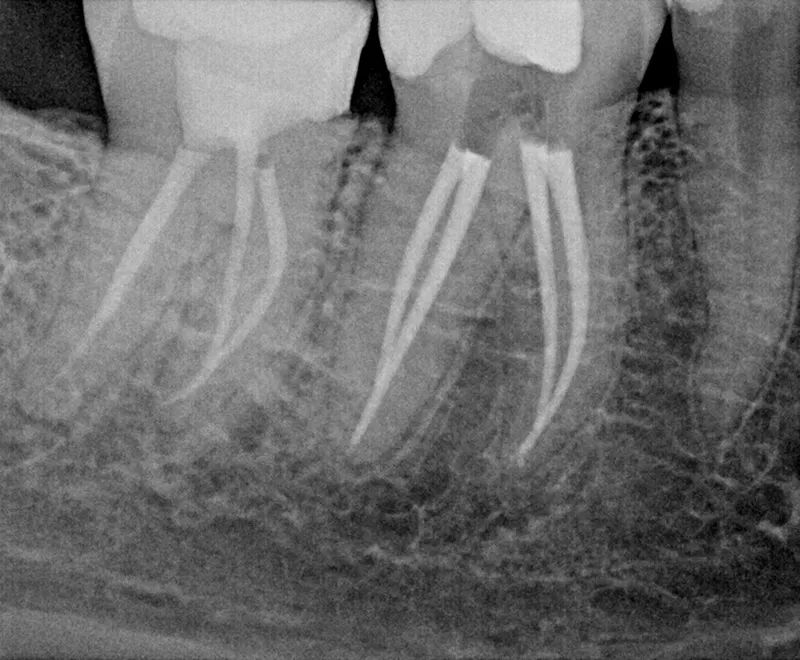

Root canal after

After